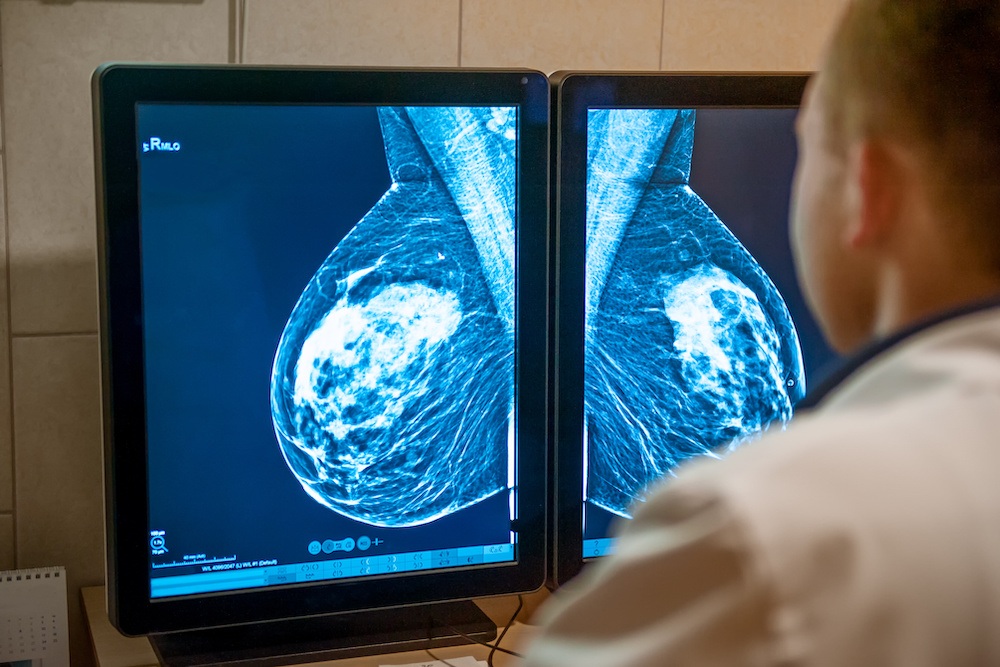

- ALIA Health, spin-off de TecSalud, y ÜMA Tech IA, Partner de Servicios de Google Cloud para el sector salud en Latinoamérica, desarrollan ALIA Health Risk Platform, una plataforma basada en inteligencia artificial que permite anticipar el riesgo de cáncer de mama a partir de mamografías.

Ciudad de México – Febrero de 2026 – En un contexto donde la mortalidad por cáncer de mama en México ha alcanzado uno de sus niveles más altos en décadas —con una tasa de 19.8 defunciones por cada 100 mil mujeres—, ALIA Health y ÜMA Tech IA anunciaron el desarrollo conjunto de ALIA Health Risk Platform, una plataforma basada en inteligencia artificial orientada a la predicción y estratificación del riesgo de cáncer de mama a cinco años, a partir de mamografías de la práctica clínica habitual.

Mammorisk+ es un modelo predictivo, entrenado con datos reales de práctica clínica y diseñado para estimar la probabilidad futura de desarrollar cáncer de mama en un horizonte de cinco años, exclusivamente en mujeres con mamografías sin hallazgos sospechosos. Su objetivo es actuar antes del diagnóstico, en la etapa donde se definen estrategias de prevención, seguimiento y personalización del tamizaje.